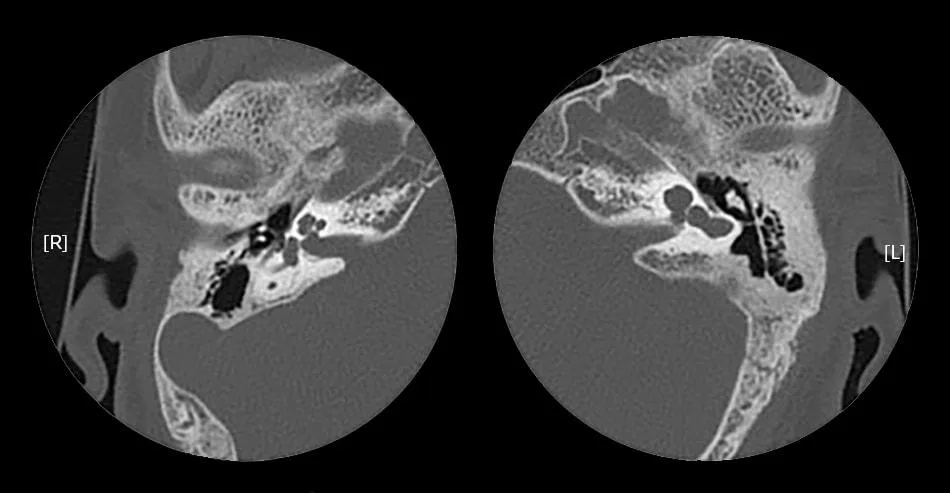

The cochlea will be located in its normal location, in the anterolateral part of the fundus of the IAC and is having normal external anatomy.

IP-I cochlea lacks the entire modiolus and interscalar septa, making it appear like an empty cystic structure. It is accompanied by an enlarged and dilated vestibule. Vestibular aqueduct enlargement is usually rare.

All patients of IP-1 will have an enlarged Internal Acoustic Canal. There may be a defect between the IAC and the cochlea due to the developmental abnormality of the cochlear aperture and the absence of the modiolus, and CSF may completely fill the cochlea.